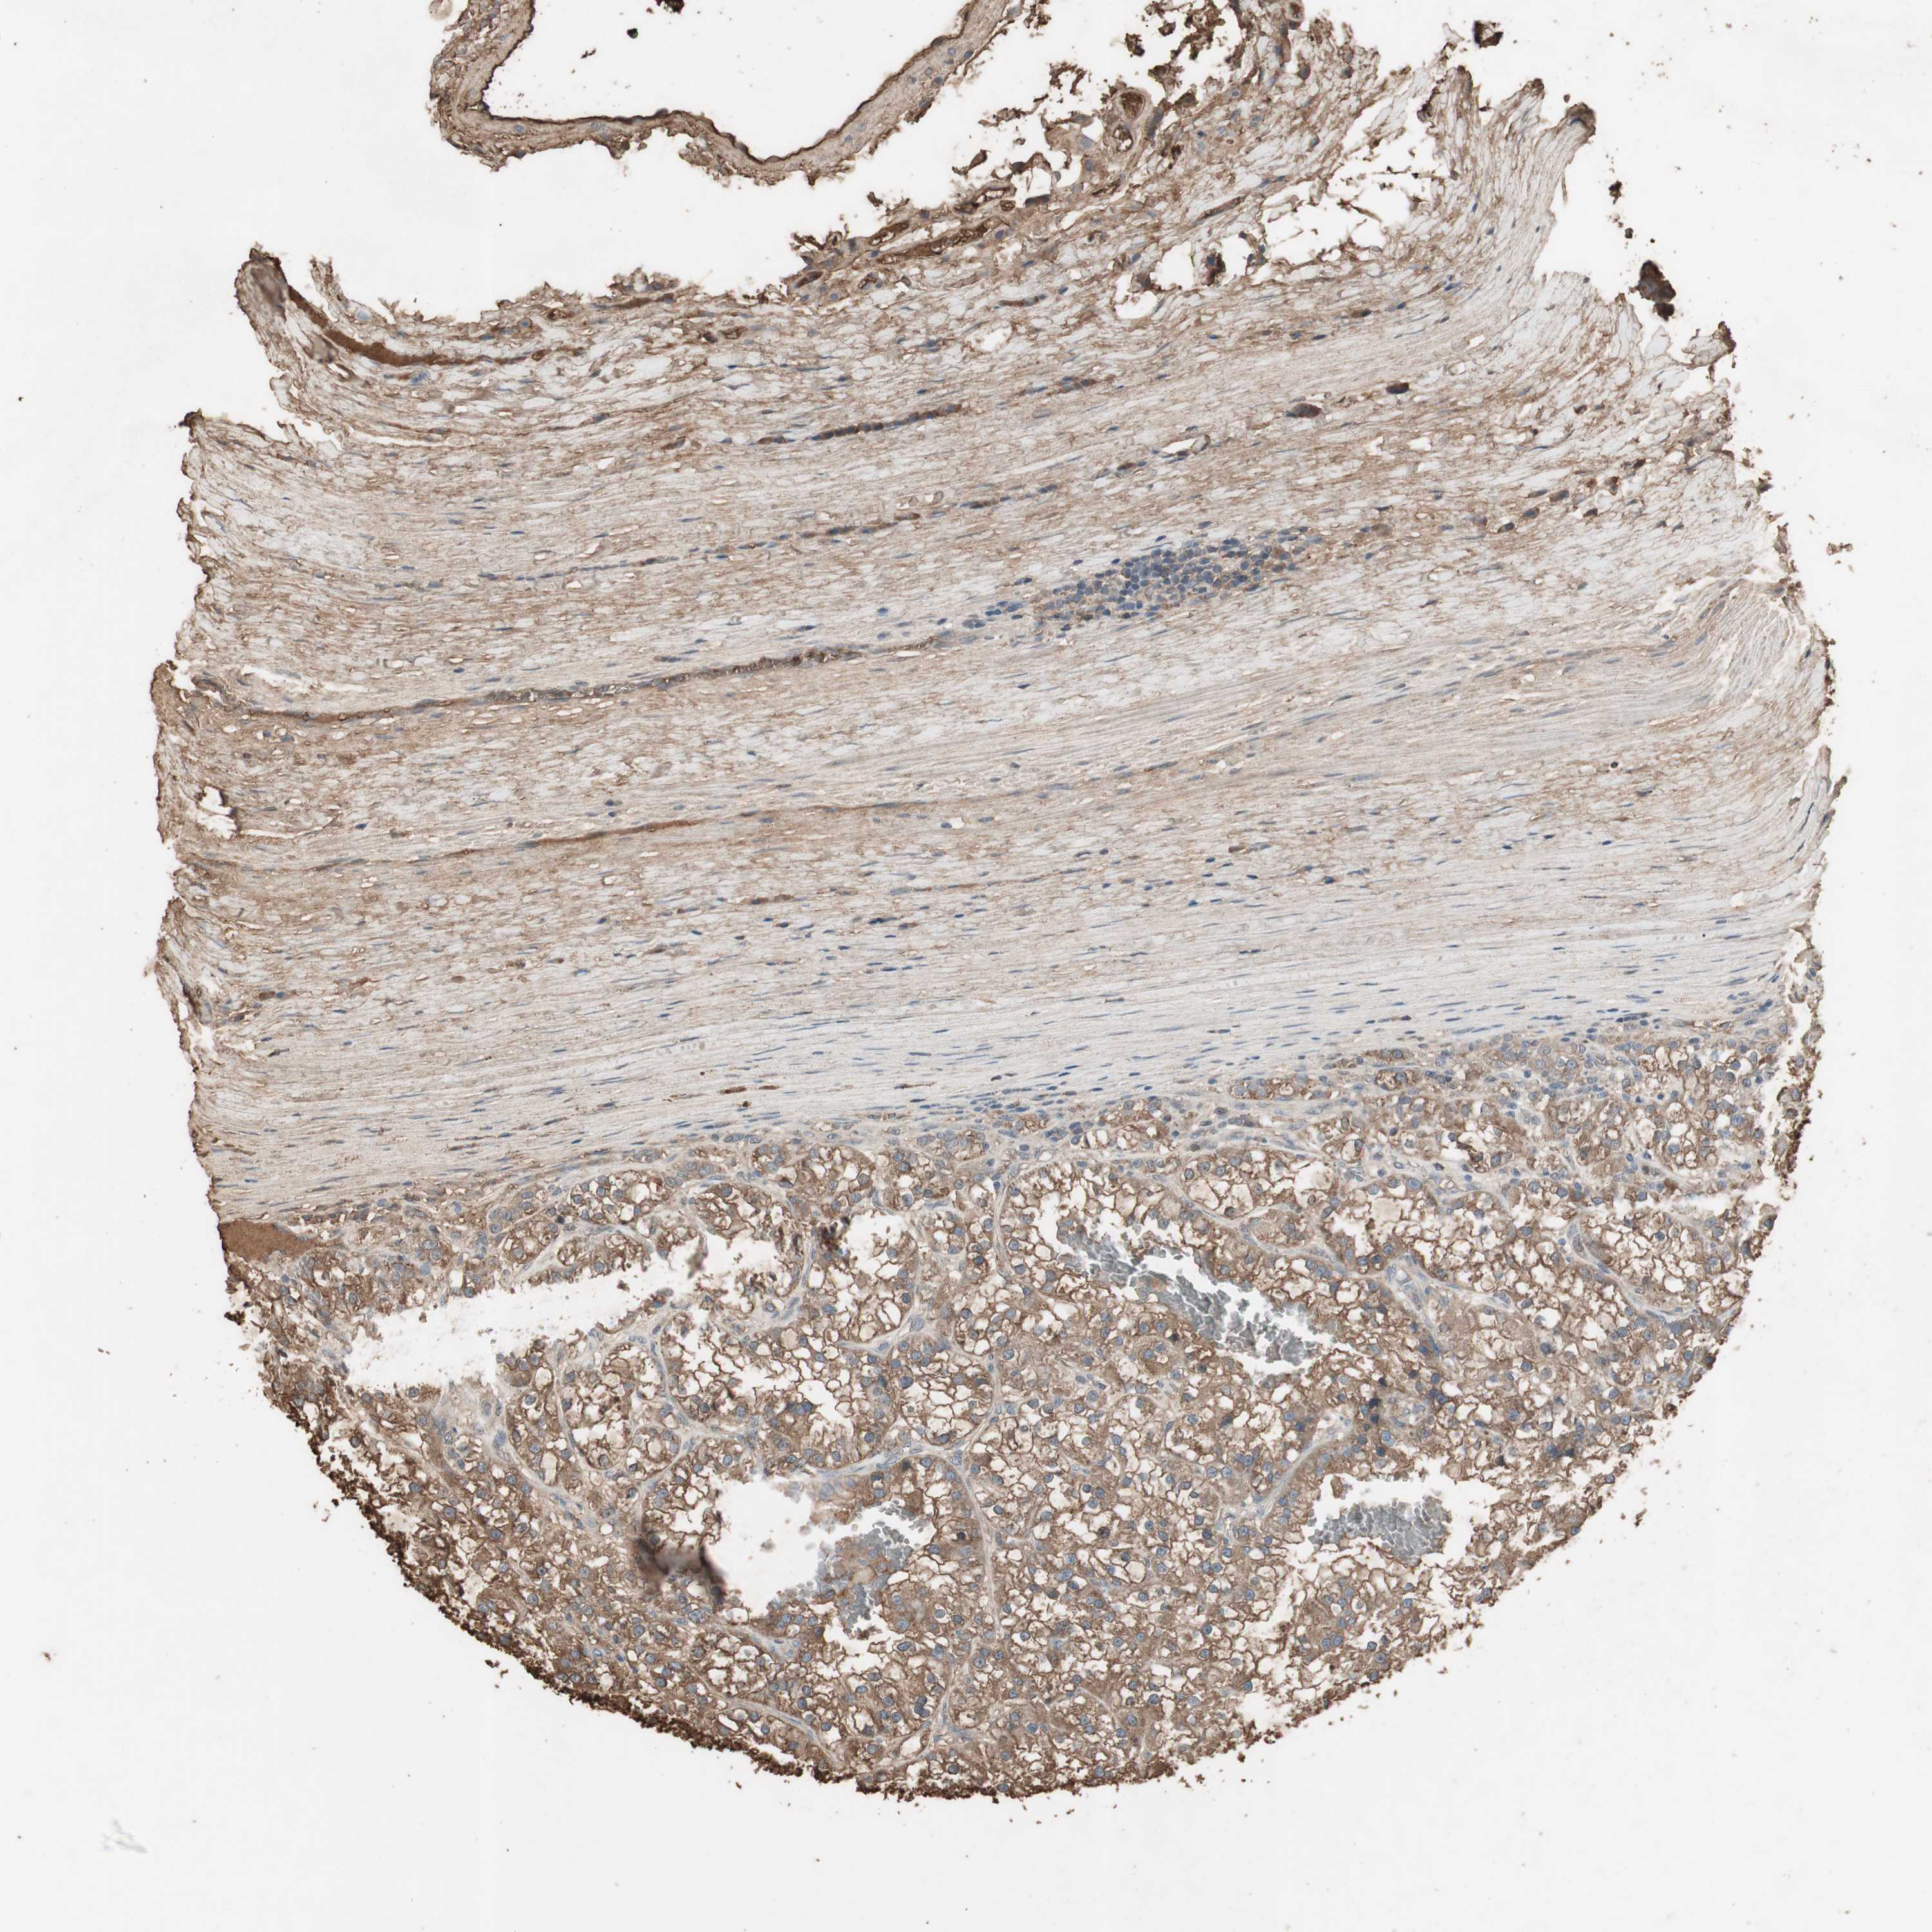

CANCER RENAL CANCER Show tissue menu

KICH TCGA KIRC TCGA KIRC VALIDATION KIRP TCGA PROTEIN RCC CPTAC PROTEIN EXPRESSION

Renal cancer